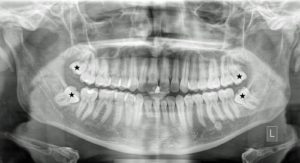

Οδοντοφατνιακή Χειρουργική – Έγκλειστα δόντια